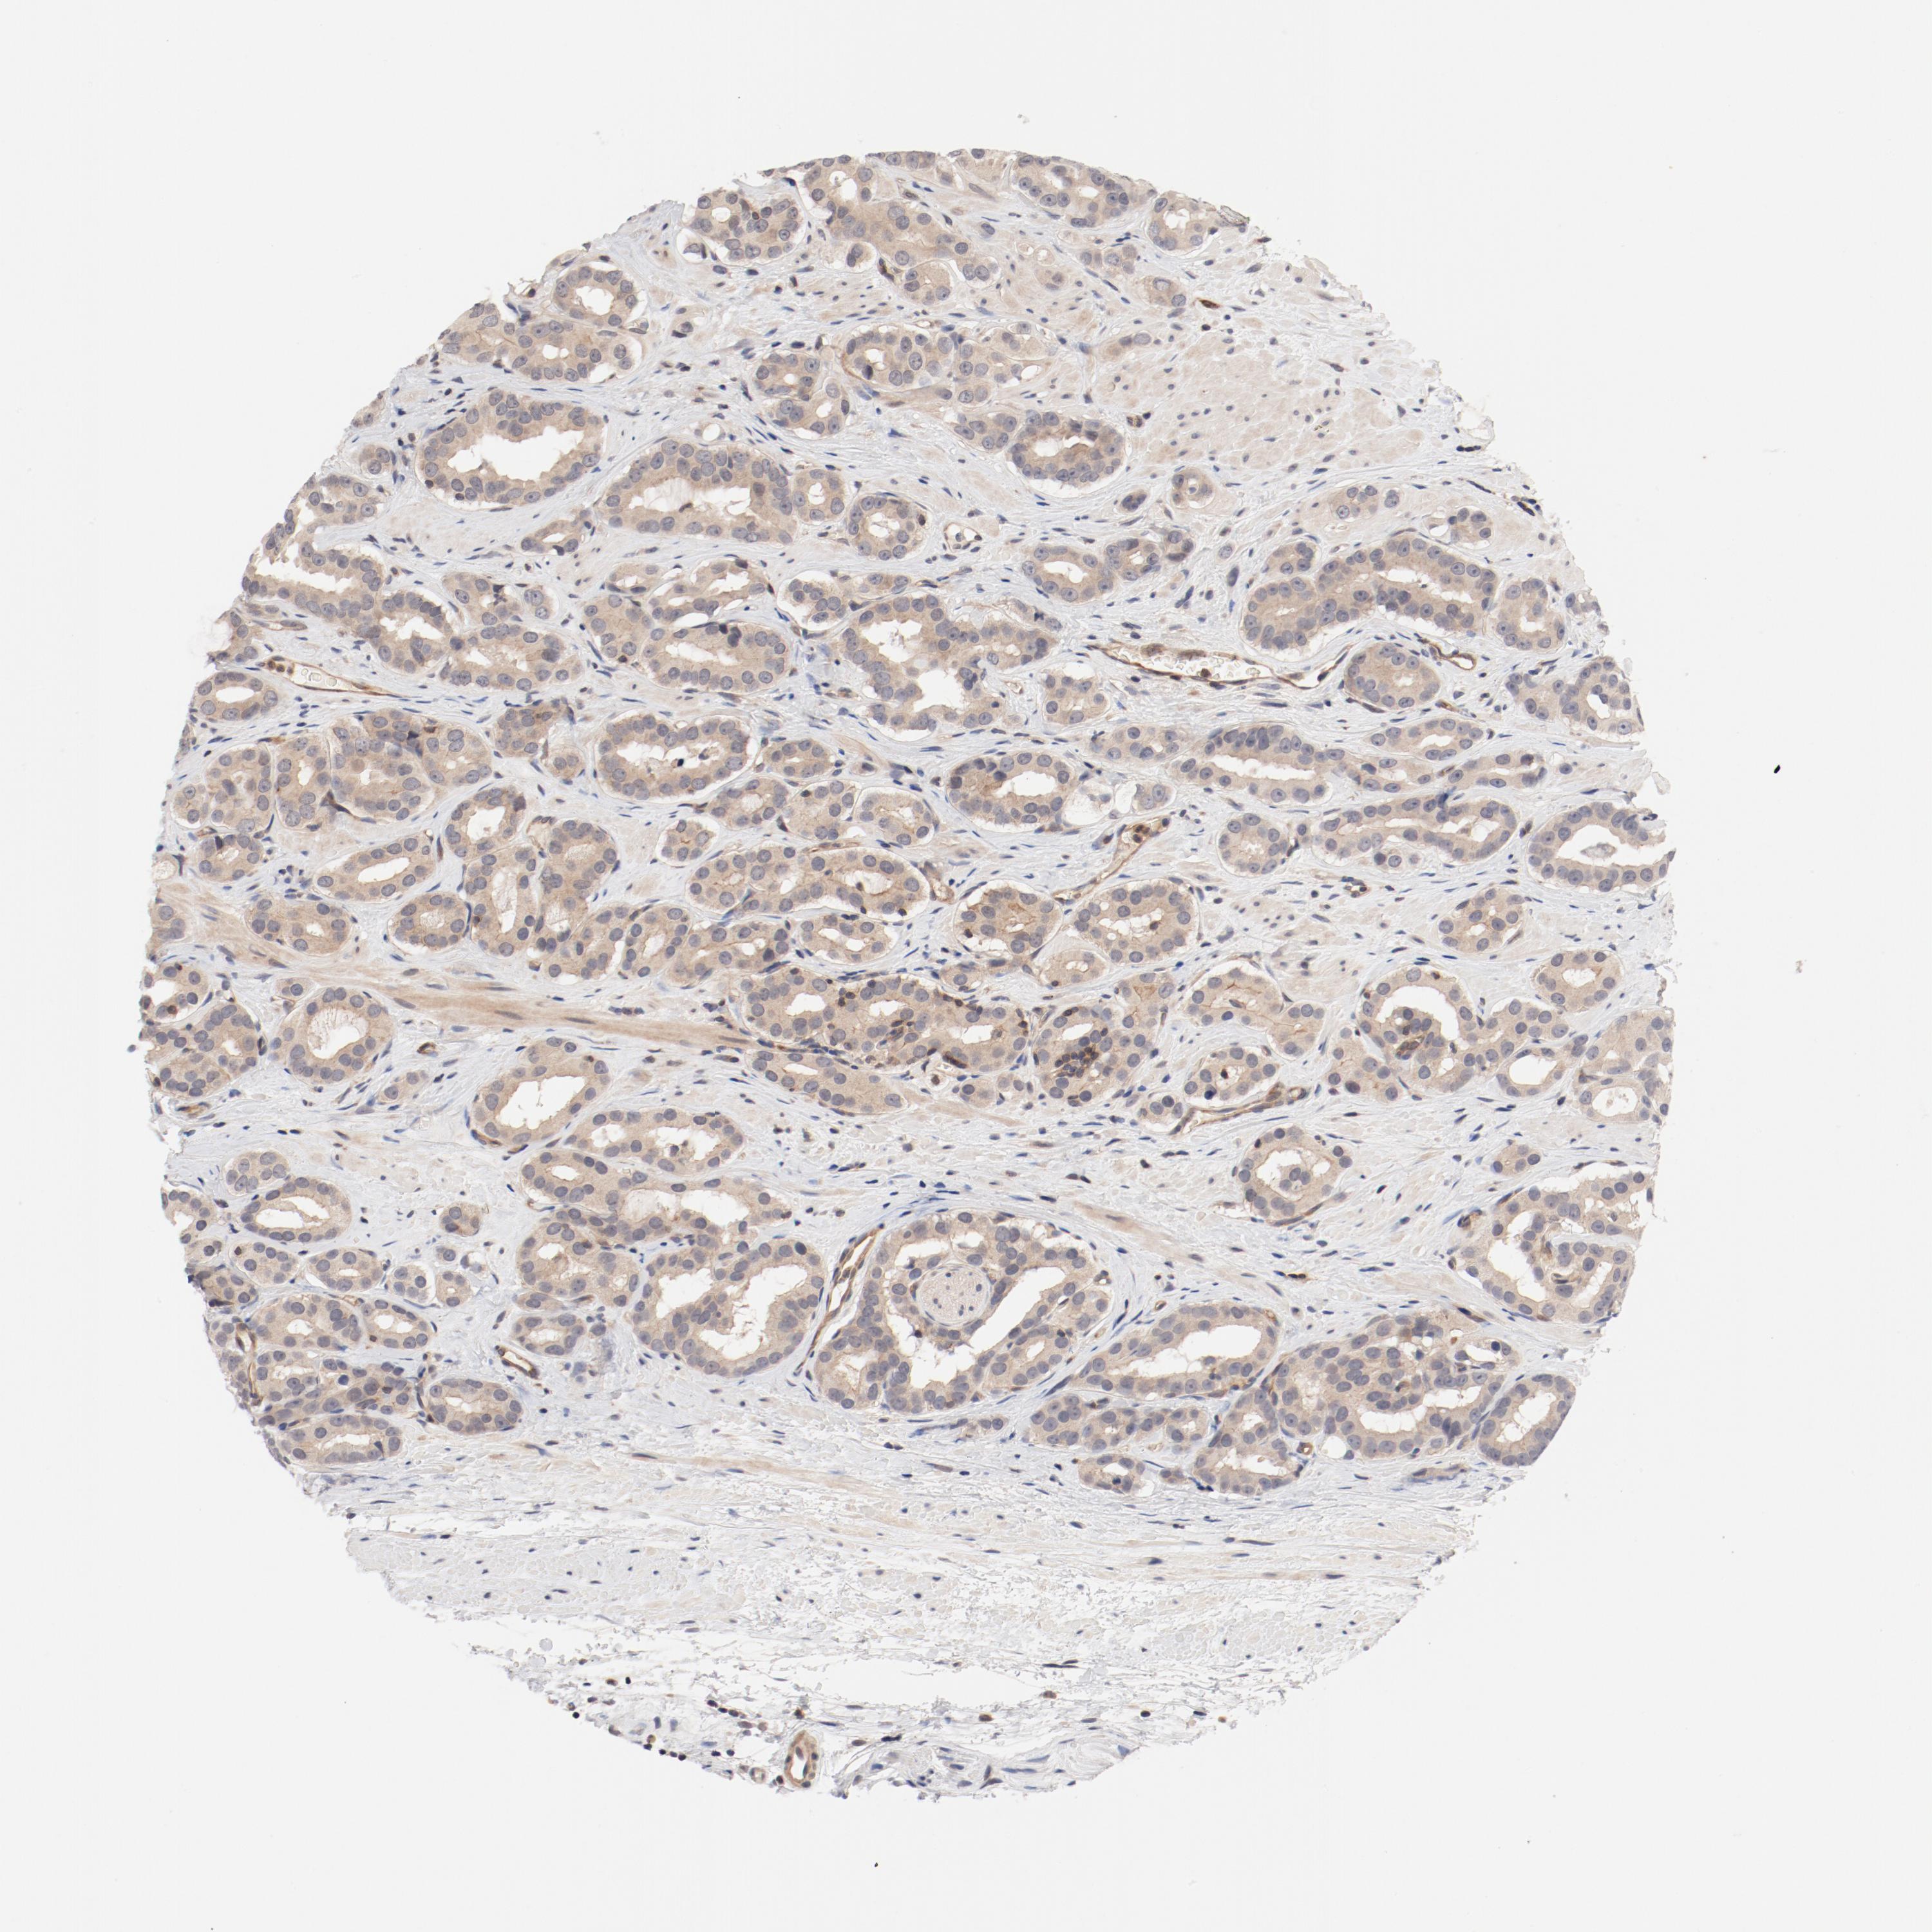

PROSTATE CANCER - Protein expressioni

A mouse-over function shows sample information and annotation data. Click on an image to view it in a full screen mode. Samples can be filtered based on level of antibody staining by selecting one or several of the following categories: high, medium, low and not detected. The assay and annotation is described here.

Antibody stainingi

Antibody staining in the annotated cell types in the current human tissue is reported as not detected, low, medium, or high, based on conventional immunohistochemistry profiling in selected tissues. This score is based on the combination of the staining intensity and fraction of stained cells.

Each image is clickable and will lead to virtual microscopy that enables deeper exploration of all samples and also displays staining intensity scores, fraction scores and subcellular localization as well as patient and tissue information for each sample.

Antibody HPA003866

Staining

High

Medium

Low

Not detected

Intensity

Strong

Moderate

Weak

Negative

Quantity

>75%

75%-25%

<25%

None

Location

Nuclear

Cytoplasmic/membranous

Cytoplasmic/membranous,nuclear

Adenocarcinoma, Low grade

Adenocarcinoma, Medium grade

Adenocarcinoma, High grade